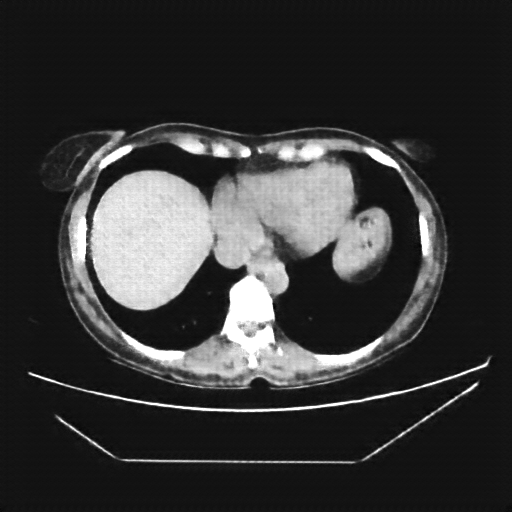

Image Grid

4Γ—3 grid: Rows show different image types (Original NATIVE, Reconstructed NATIVE, Original VENOUS, Generated VENOUS), Columns show windowing techniques (No Window, Lung Window, Mediastinum Window)

Reconstructed NATIVE CT scan (cycle consistency)

Full window (WL 1023.5, WW 4095 β†’ Low βˆ’1024, High +3071)

Actual HU range: [-832.9, 629.2]

Lung window (WL -600, WW 1500 β†’ Low βˆ’1350, High +150)

Actual HU range: [-832.9, 150.0]

Mediastinum window (WL 40, WW 400 β†’ Low βˆ’160, High +240)

Actual HU range: [-160.0, 240.0]